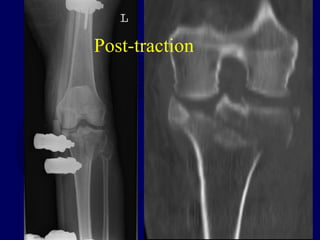

Pre-traction

Post-traction